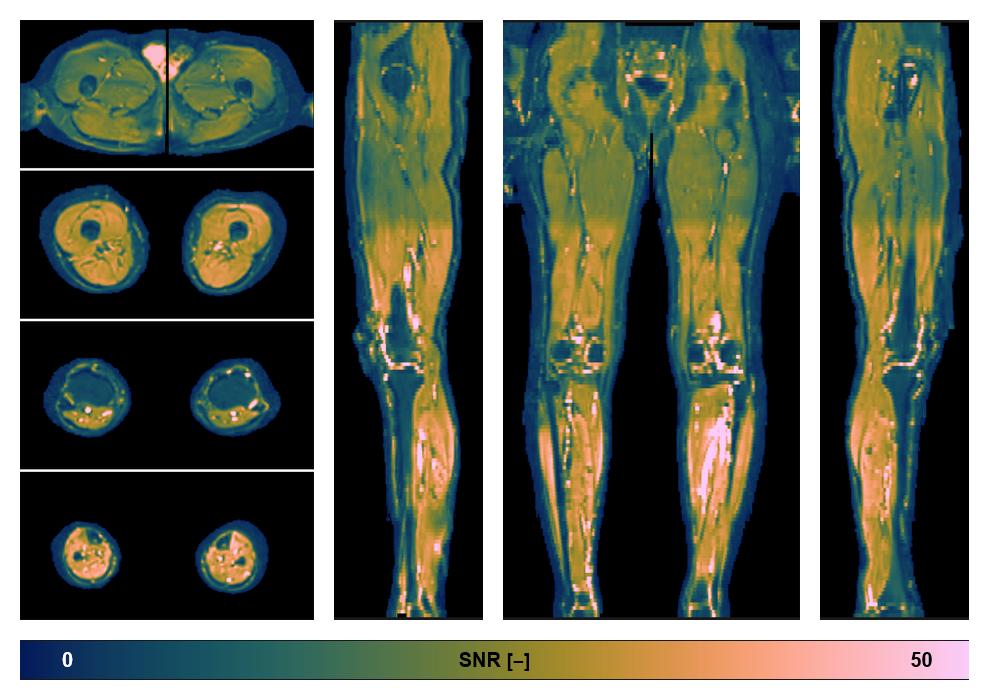

• SNR of the unweighted image

SNR distribution of the unweighted diffusion data.